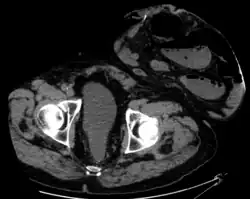

CT scan of same patient, showing intestines within the hernia.

Parastomal hernia is the most common late complication of stomata through the abdominal wall, occurring in 10 to 25% of the patients.[1]